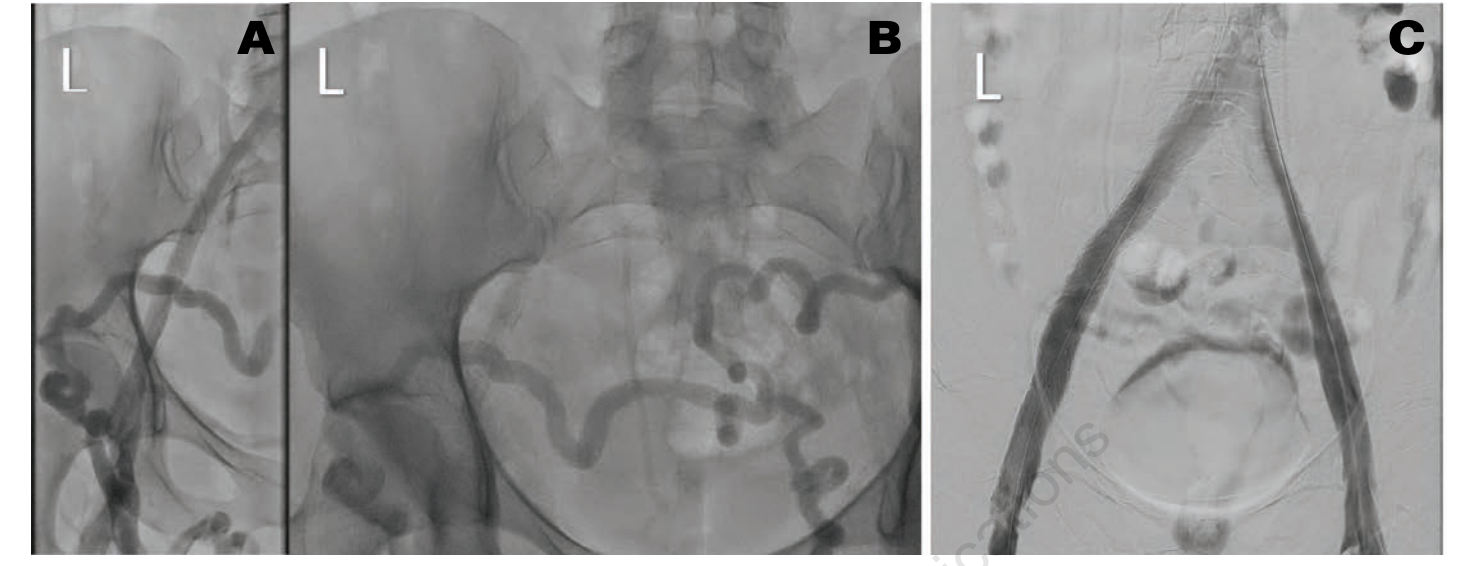

A 39-year-old woman with a history of recurrent deep vein thrombosis (DVT), pulmonary embolism (PE), and protein C deficiency on oral anticoagulation (OAC) was referred to our clinic for chronic bilateral lower extremity swelling, redness, and varicose veins. She was initially diagnosed with DVT and PE in 2003, for which she was on OAC with warfarin. Her warfarin was discontinued 6 months later, and she did well until 2018 when she had a recurrent DVT and PE following an 8-hour plane ride. At that time, a workup revealed a protein C deficiency, and she had been on OAC with apixaban 5 mg twice daily ever since. Her leg swelling, redness, and pain became severe a few weeks before presentation, which was aggravated by standing for long periods. She also complained of frequent dyspareunia and periodic pelvic pain. On physical examination, she was noted to have varicose veins on both legs, 2+ pedal edema up to the level of the thigh, and redness in both legs. We ordered a venous ultrasound (US) of the lower extremity to assess for reflux and to rule out DVT. We ordered a magnetic resonance angiography (MRA) with the suspicion of a central venous obstruction and PCS. Her US showed a chronic, nonocclusive thrombus in the left common femoral vein (CFV). Her MRA showed effacement of the proximal left iliac vein by the right common iliac artery, which was consistent with May-Thurner syndrome (Figure 1). In addition, the MRA showed varices of the anterior pelvic wall. We performed venography with intravascular US (IVUS)-guided percutaneous transluminal angioplasty (PTA) and stent placement. US-guided access was obtained from both right and left popliteal veins, and 8 Fr sheaths were inserted. Contrast venography was performed to both the deep femoral and iliac veins, demonstrating vessel patency throughout with visually apparent luminal narrowing in the left iliac vein. IVUS confirmed a 40% compression of the right external iliac vein (EIV) and a diffuse 80% fibrotic stenosis of the left common iliac vein (CIV) to CFV (Figure 2A). Extensive pelvic collaterals were also noted (Figure 2B). We performed PTA of the left CIV with a 16 mm x 40 mm Atlas Gold balloon (BD). Following balloon angioplasty, through the 8 Fr sheath, we deployed a 16 x 140 mm Zilver Vena stent from the left CIV into the EIV and deployed another 16 x 60 mm Zilver Vena stent overlapping with the first stent from the EIV into the CFV. The stents were post-dilated with the same Atlas Gold balloon, and a postprocedure venogram and IVUS showed excellent results, with complete resolution of the pelvic collaterals (Figure 2C). She was discharged home on clopidogrel 75 mg daily in addition to the apixaban 5 mg twice daily that she was already on. On a follow-up visit 1 month later, the patient reported significant reduction of her lower extremity edema, pain, and redness. On a 6-month follow-up, she reported complete resolution of these symptoms as well as pelvic pain and dyspareunia.